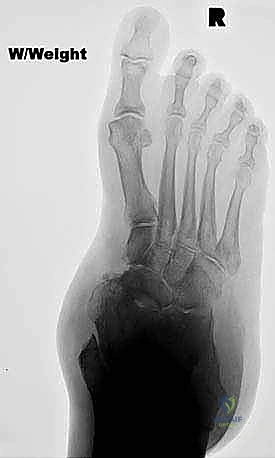

* تشوه ملحوظ في شكل القدم: تسطح كامل للقوس، وانحراف واضح للكعب نحو الخارج (Valgus).

* تصلب مفاصل القدم (Rigidity)، حيث لا يمكن للطبيب إعادة القدم إلى وضعها الطبيعي يدوياً أثناء الفحص.

تُجرى هذه العملية المعقدة تحت التخدير العام أو النصفي، وتستغرق عادة ما بين ساعتين إلى ثلاث ساعات. يحرص الأستاذ الدكتور محمد هطيف على اتباع بروتوكول جراحي دقيق لضمان أعلى نسب النجاح:

الخطوة الأولى: التجهيز والشق الجراحي

يتم وضع المريض في وضع الاستلقاء، ويتم استخدام عاصبة (Tourniquet) لتقليل النزيف. يقوم الدكتور هطيف بعمل شق جراحي واحد منحني على الجانب الإنسي (الداخلي) للقدم، يمتد من أسفل الكعب الداخلي وصولاً إلى العظم الزورقي.